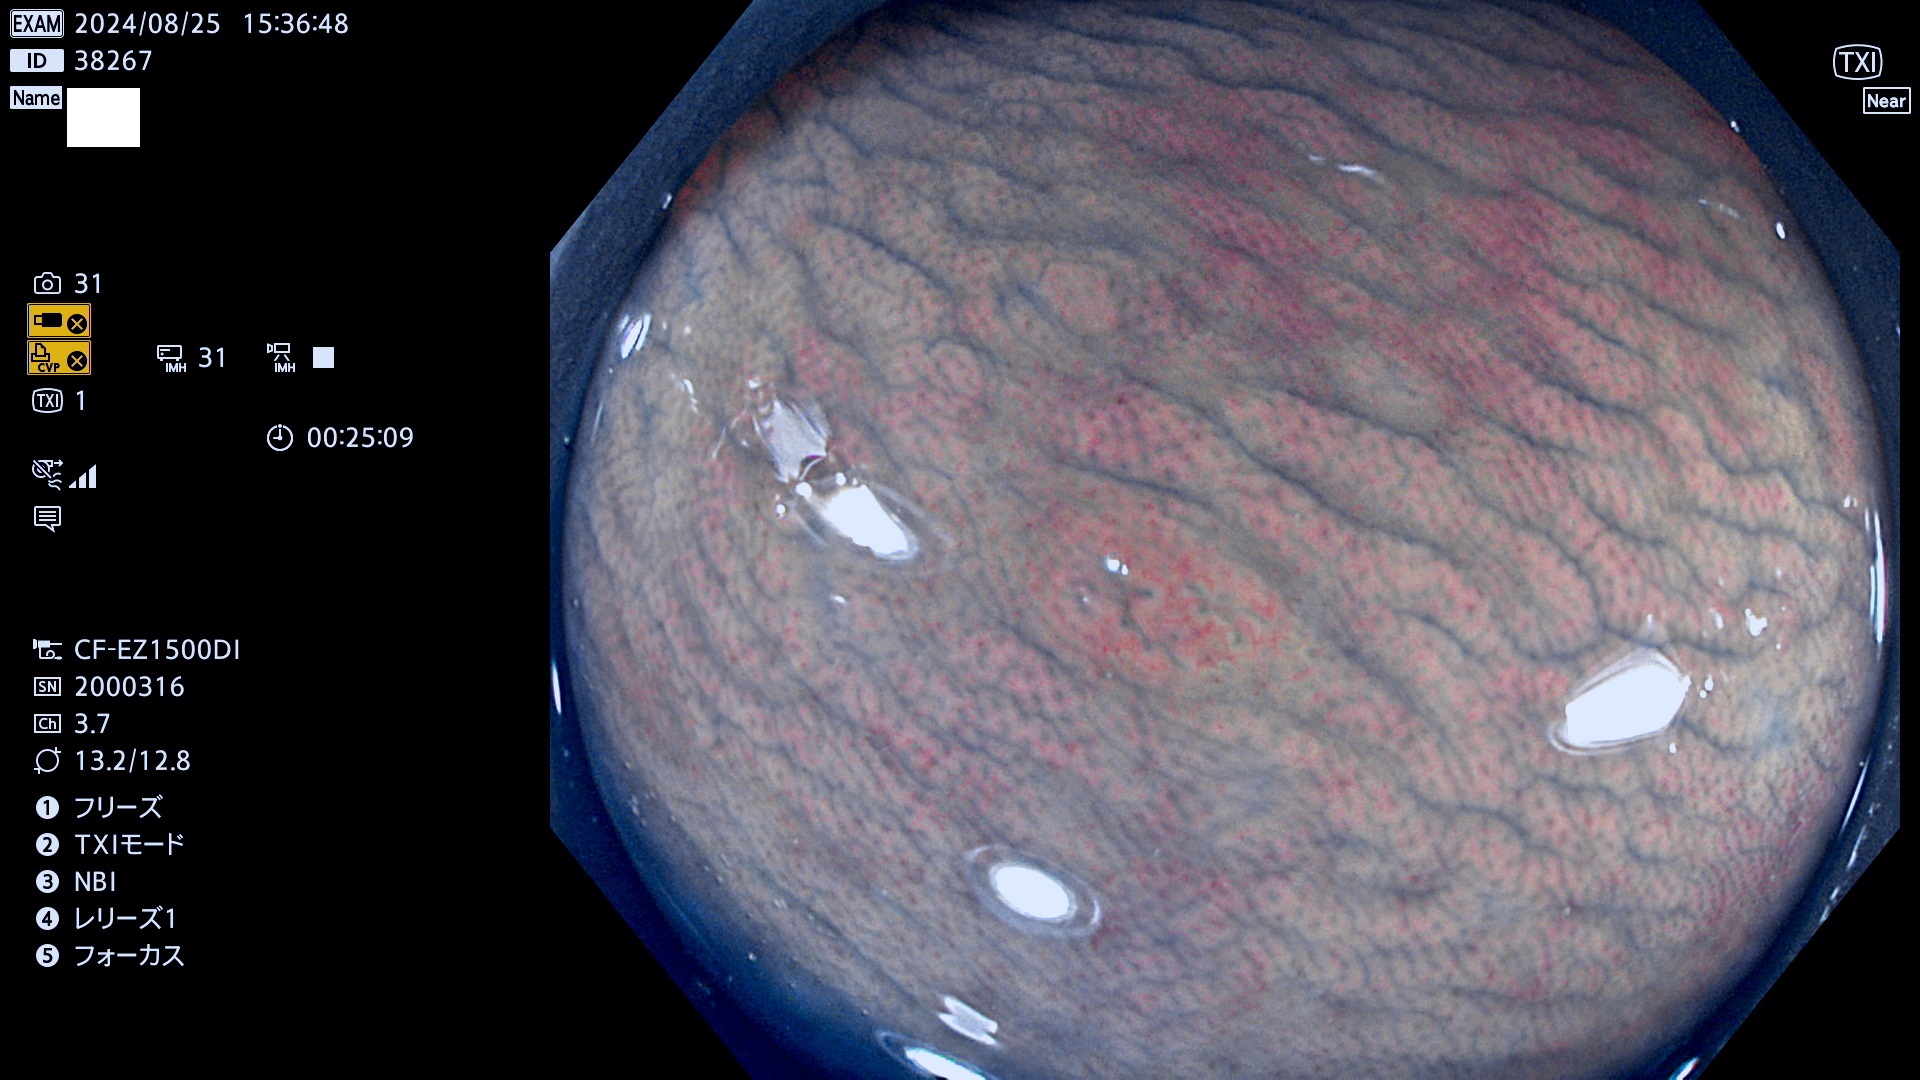

完全に平坦な物をUb、陥凹している物をUcと呼びます。最も発見が難しく危険な病変です。

毎週の検査(木・金・土・日)に発見されたUb、Uc型・腺腫を、その週の日曜の夜にUPし1週間、提示します。

抽出の対象期間 2024年8月22日〜8月25の4日間(33件の検査)7件 (7/33=21%)